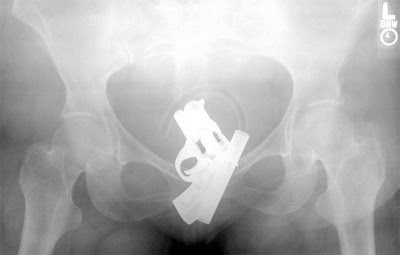

Aici, o… doamnă şi-a introdus un pistol în vagin. :-s Mă rog, e o brichetă în formă de pistol, da’ totuşi…